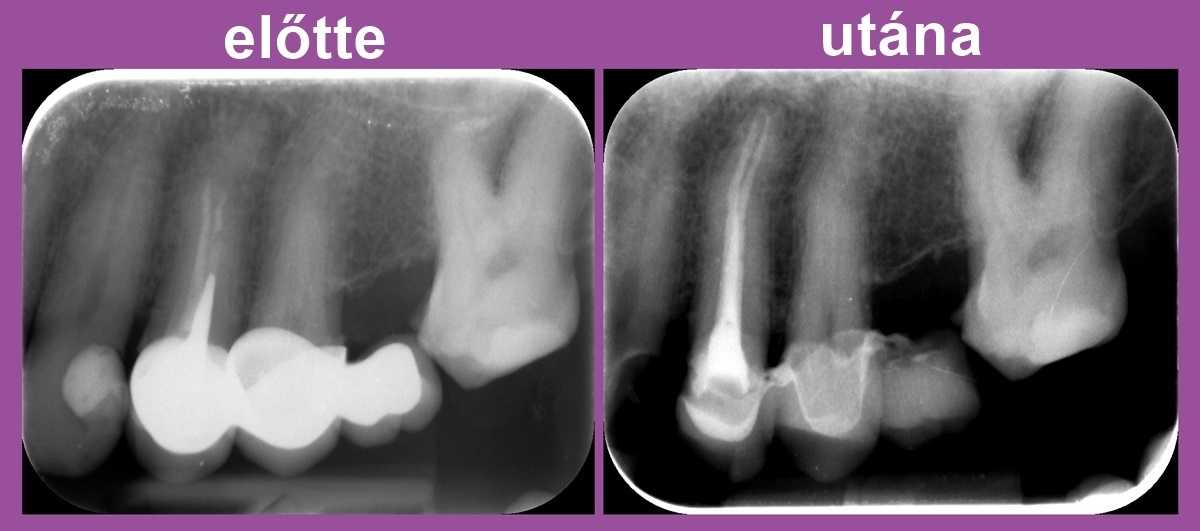

A képen látható, hogy a bal felső négyes fog a híd alatt csappal van megerősítve, és a gyökértömés a csatornákban nem ér végig. Ennek következtében a gyökércsúcs körül gyulladás alakult ki. Nyilvánvalóvá vált, hogy a híd levételére, a csap és a gyökértömés mikroszkóppal történő eltávolítására lesz szükség.

A gyökércsatornák gyógyszeres lezárása után ideiglenes híddal láttuk el a pácienst.

A második alkalommal a csatornák újabb fertőtlenítésére, tisztítására került sor. Ezek után elkészült az új gyökértömés, melyhez ismét igénybe vettük a mikroszkóp segítségét.

A fog panaszmentessé vált – így hát megmenekült attól, hogy el kelljen távolítani!